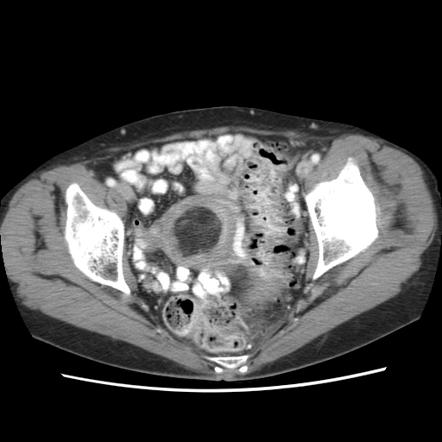

- Tomografía computarizada: este examen utiliza rayos X para obtener imágenes transversales del cuerpo y detectar la presencia de tumores.